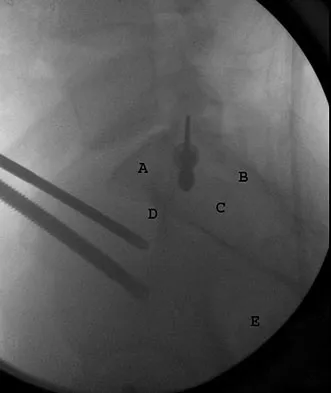

A 7-year-old patient has had a painless limp for several months. Examination reveals pain and spasm with internal rotation, and abduction is limited to 10 degrees on the involved side. Management consists of 1 week of bed rest and traction, followed by an arthrogram. A maximum abduction/internal rotation view is shown in Figure 40a, and abduction and adduction views are shown in Figures 40b and 40c. The studies are most consistent with

Explanation

The radiographs show classic hinge abduction. The diagnostic feature is the failure of the lateral epiphysis to slide under the acetabular edge with abduction, and the abduction view shows medial dye pooling because of distraction of the hip joint. Persistent hinge abduction has been shown to prevent femoral head remodeling by the acetabulum. Radiographic changes are characteristic of severe involvement with Legg-Calve-Perthes disease.The Catterall classification cannot be well applied without a lateral radiograph, but this degree of involvement would likely be considered a grade III or IV. Because the lateral pillar is involved, this condition would be classified as type C using the Herring lateral pillar classification scheme.